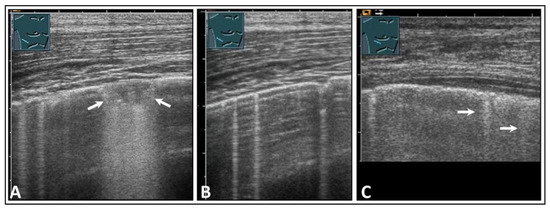

2. Basic Principles and Examination Technique